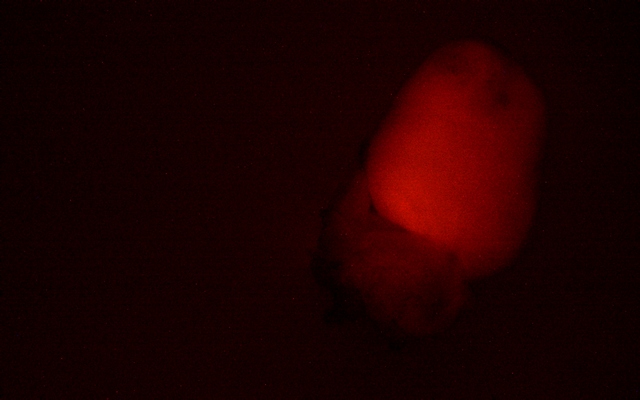

MZX81显微镜以其出色的明场和荧光成像能力,为科研人员提供了清晰锐利的观察体验。在明场模式下,心脏组织的细微结构一览无余,细胞轮廓分明,为后续的深入分析奠定了坚实基础。而切换到荧光模式时,MZX81又能够精准捕捉荧光标记信号

荧光标记小鼠心脏